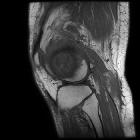

MRI

The “penumbra sign” on magnetic resonance (MR) imaging is useful for discriminating subacute osteomyelitis from other bone lesions. The penumbra sign is a rim lining of an abscess cavity with higher signal intensity than that of the main abscess on T1-weighted images with strongly and rapidly enhance after contrast.